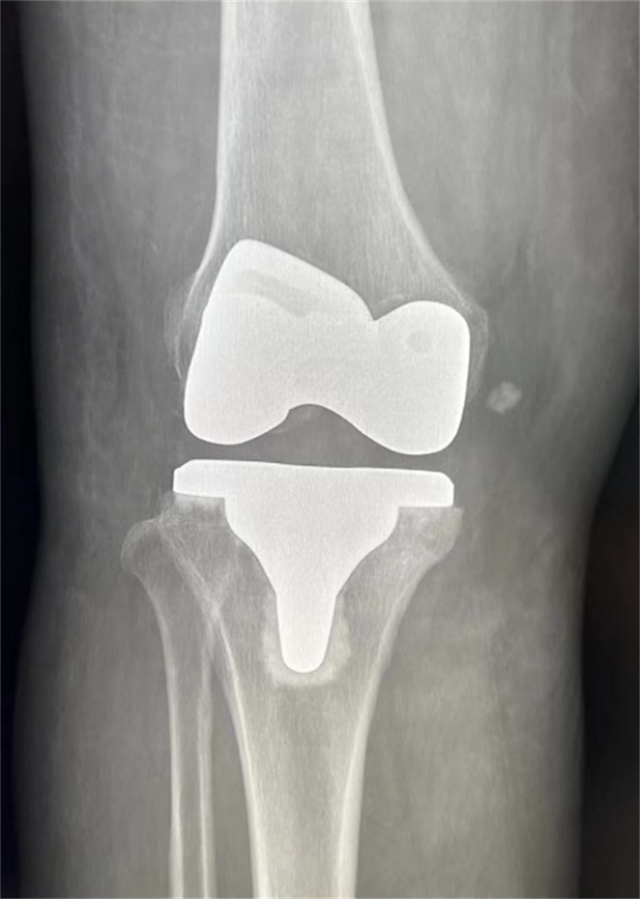

患者术后影像资料

患者术后第3天,膝关节可屈曲120°